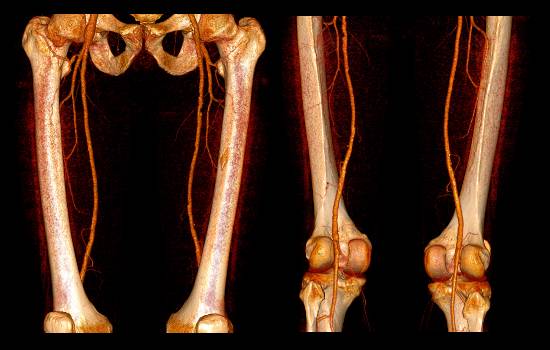

При отсутствии противопоказаний специалист выбирает один из двух видов ангиографии – артериальную или венозную. Выбор зависит от того, какие именно сосуды подлежат исследованию. В обоих случаях используются разные точки для прокола, через которые вводится контрастное вещество. Если врачу нужно уточнить ранее установленный диагноз, назначается КТ (компьютерная томография) ангиография сосудов нижних конечностей. Эта методика считается более эффективной и точной по сравнению с традиционной ангиографией.

Процедура включает в себя создание послойных изображений нижних конечностей. Затем формируется компьютерная 3D-модель, что позволяет врачу получить детальное представление о состоянии сосудов. Даже если потребуется сделать несколько снимков, доза излучения, которую получает пациент, значительно меньше, чем при использовании рентгеновского метода.

Компьютерная томография (КТ) с контрастированием также используется для визуализации сосудов. Этот метод позволяет получить высококачественные изображения и оценить состояние сосудов в трехмерном формате. Однако, КТ-ангиография требует введения контрастного вещества, что может вызвать аллергические реакции у некоторых пациентов. Кроме того, этот метод связан с облучением, что делает его менее предпочтительным для повторных исследований.